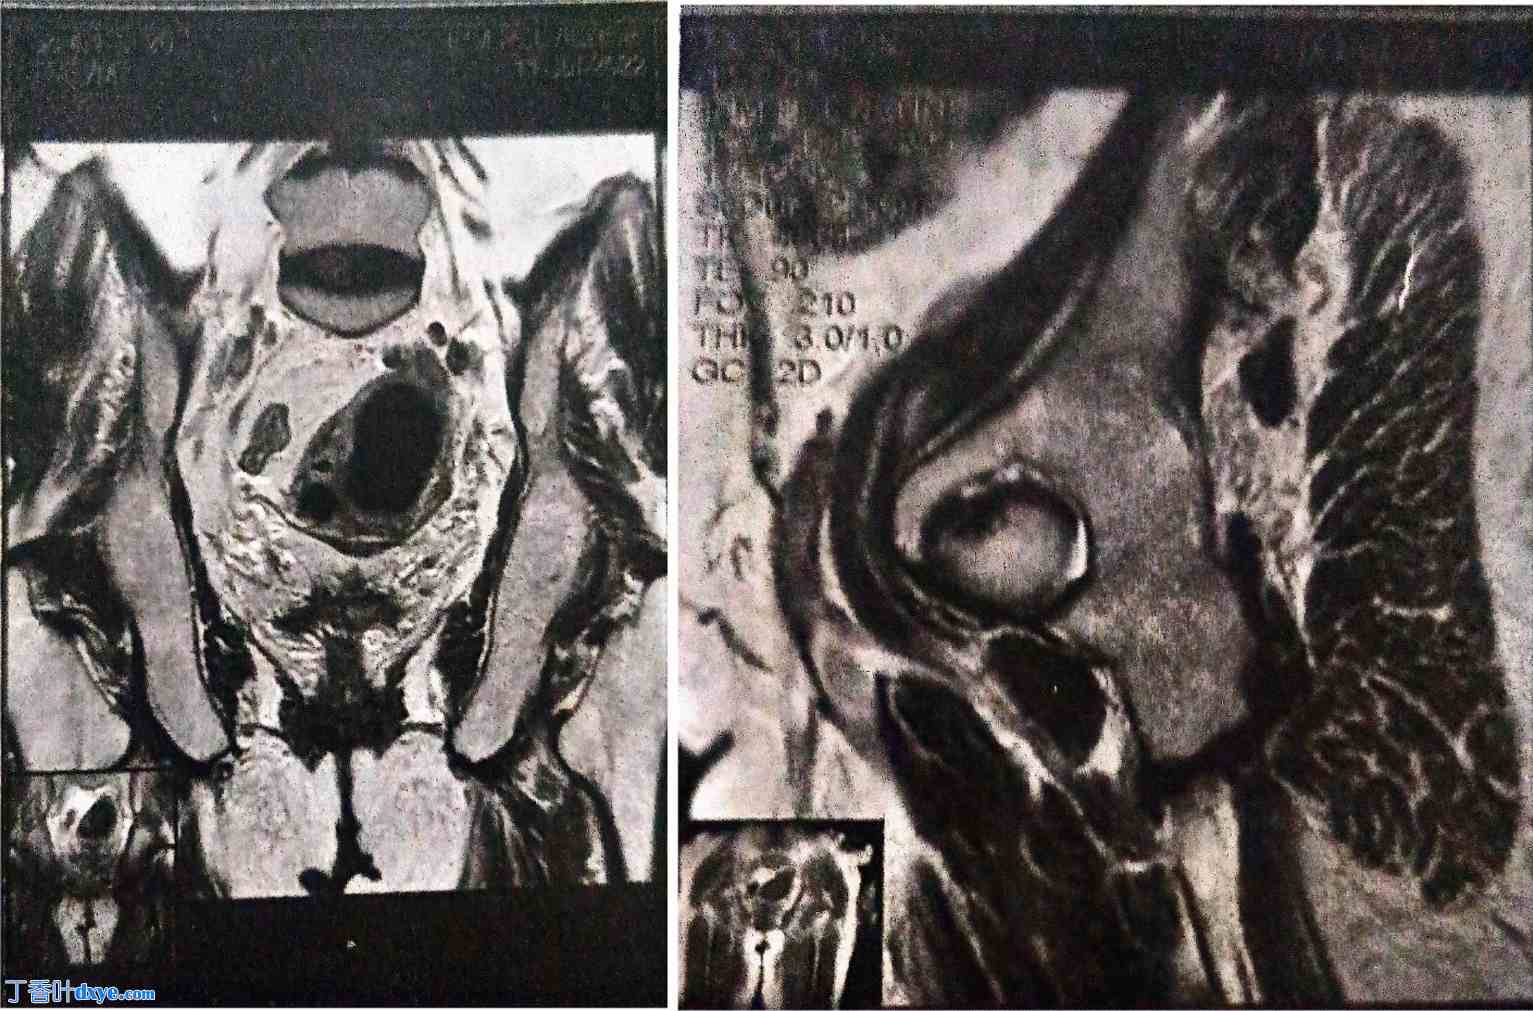

2021年1月,术后行腹盆部CT扫描随访时,意外发现左侧附件区有一个4厘米的实性囊性肿块,高度怀疑为恶性肿瘤。经阴道超声和盆腔MRI检查证实该肿块为恶性肿瘤,根据卵巢附件报告和数据系统(O-RADS)分类为5级(高度怀疑恶性肿瘤)(图1)。

图 1.

腹盆部磁共振成像显示左侧卵巢实性囊性肿块,根据卵巢附件报告和数据系统 (OARDS) 分类为 5 级。